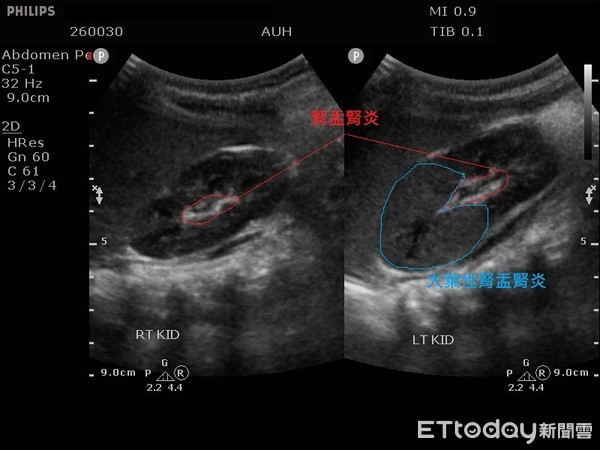

Tiến hành siêu âm thận, bác sĩ cũng phát hiện cả hai quả thận của bé đều bị viêm. Lấy nước tiểu xét nghiệm là do vi khuẩn E. coli gây ra tình trạng viêm mô kẽ thận ở thận trái và viêm thận bể thận cấp tính ở cả hai quả thận.

Viêm mô kẽ thận ở thận trái và viêm thận bể thận cấp tính ở cả hai quả thận